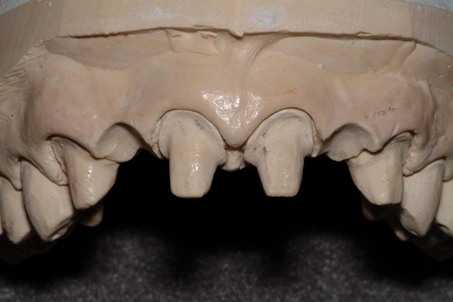

(9.) Ovate pontic sites created on the master cast by the laboratory.

Figure 9